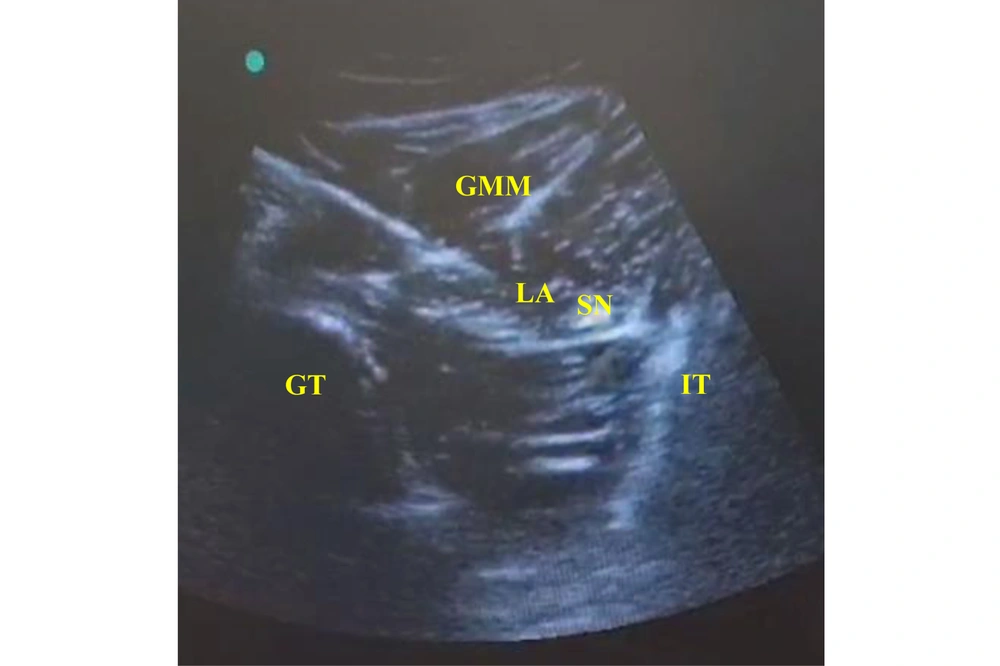

In the SNB Group: The patients received US-guided subgluteal sciatic nerve block after anesthesia induction. Each patient was placed in the lateral position, with the limb at which the nerve block was done in the uppermost position. After adequate skin disinfection with povidone-iodine, the probe was placed at the level of the gluteal crease midway between the 2 bony landmarks, the greater trochanter and ischial tuberosity (hyperechoic lines with acoustic shadowing); the gluteus maximus muscle was identified, and the sciatic nerve was hyperechoic and often elliptical and deep to this muscle (Figure 2). An echogenic 22-gauge 5-cm needle was inserted utilizing the in-plane approach from lateral to medial targeting the sciatic nerve; the LA [bupivacaine 0.25% (0.3 mL/kg) without exceeding a maximum volume of 20 mL] was injected in increments of 1 mL every 5 seconds to surround the whole nerve circumference. Patients’ follow-up after the block (during and after surgery) was performed by an anesthesiologist blinded to the type of regional blockade.